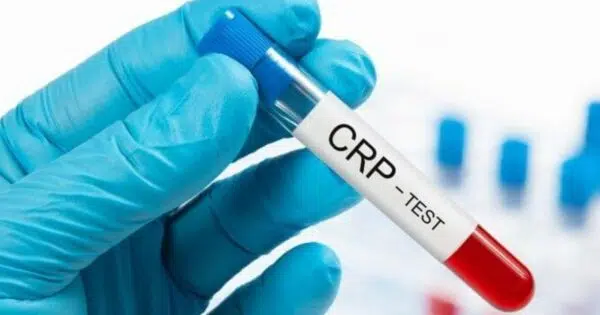

Comment faire baisser le taux de crp naturellement ?

La CRP est l’une des substances produites par le foie de l’homme. Une grosse quantité de CRP peut entraîner une inflammation accrue dans le corps, ce qui peut alors créer un risque de maladie cardiaque. Il est alors important de maîtriser son niveau de CRP. Cet article vous aidera à ...Pain de mie périmé : peut-on encore le consommer ?